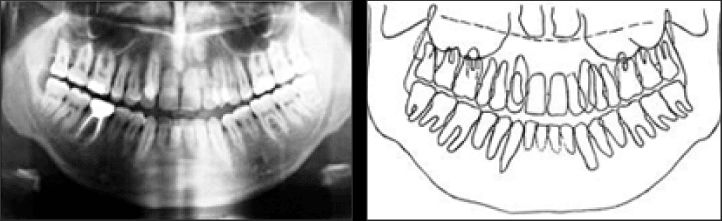

كما ينبغي الانتباه أثناء تصوير الأشعة البانورامية لرفع اللسان ليلامس سقف الفم ليغلق كامل المجرى التنفسي في الفم فلا يتبقى أي هواء في الفم، ولا يكفي فقط رفع طرف اللسان.